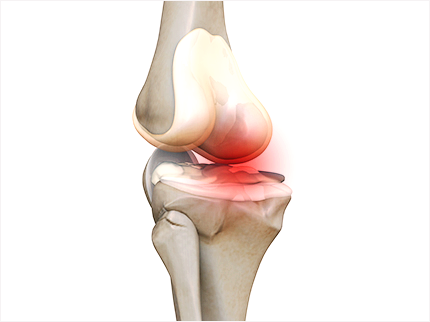

골관절염은 연골에 손상이 가해지면서 관절의 간격이 줄어들고 뼈가 서로 맞닿아 통증을 동반하는 질병입니다. 콘드로이친은 질병과 외부 충격으로부터 체내의 조직을 안전하게 보호하고 동시에 조직 표면에 가해지는 충격 등을 이겨낼 수 있도록 탄성을 주는 프로테오글리칸(Proteoglycan)이라는 물질의 생성을 돕게 됩니다. 때문에 콘드로이친은 특히 골관절염에 효과가 있습니다.

콘드로이틴황산염은 연골 구성 성분의 하나이고 연골세포를 자극해 연골조직을 정상적으로 복원하는데 효능이 있다고 알려져 있습니다. 특히 외부 자극에 의해 문제가 되는 TNF-알파 등 사이토카인의 작용을 억제하는 역할을 합니다. 그리고 지속적인 염증 유발 및 연골 파괴 유발 사이토카인을 감소시켜 관절 내 염증 및 통증반응 그리고 연골파괴를 막아주는데 도움을 줍니다.

콘드로이친은 글루코사민과 같이 연골 성분의 일부로써 연골, 힘줄, 뼈, 각막 등의 신체 결합 주위에 널리 퍼져 있습니다. 관절 연골에 필요한 영양을 공급하고 연골을 분해하는 효소를 억제함으로써 관절 건강에 도움을 줍니다.

그렇지만 이미 연골의 손상이 심각하다면 관절 영양제를 먹어도 손상된 연골을 복구할 수는 없습니다. 다만 관절의 손상 속도를 지연시키는 보조제 역할 정도로 활용할 수 있습니다.